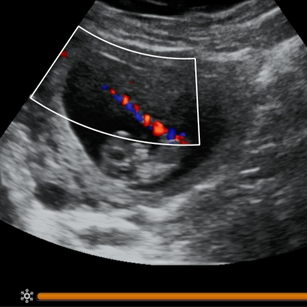

10 Weeks Pregnant

Size: ~1.2 inches (3 cm), the size of a Strawberry!

Baby starts small spontaneous movements, though not yet felt.